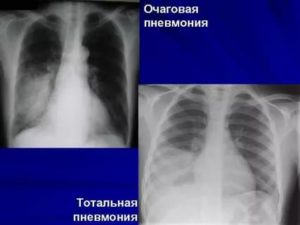

Рентгенография. Дает возможность определить наличие жидкости, если ее количество составляет от 300 — 400 мл. Также данный метод позволяет обнаружить опухолевые очаги и метастазы, которые распространились в плевральную область и лимфатические узлы. Рентгенографию осуществляют и для контроля состояния пациента после процедуры эвакуации (удаления) жидкости из легких.

- Рентгеноскопия. Проблемные участки на рентгенограмме выглядят как однородное затемнение,

Важно! От рентгеновских снимков не будет пользы при слабовыраженном заболевании, поскольку количество крови или лимфы минимально (100-200 мл).